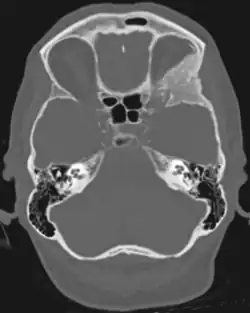

Sphenoid wing meningiomas are diagnosed by the combination of suggestive symptoms from the history and physical and neuroimaging by magnetic resonance imaging (MRI) or computer averaged tomography (CT). Tumors growing in the inner wing (clinoidal) most often cause direct damage to the optic nerve leading especially to a decrease in visual acuity, progressive loss of color vision, defects in the field of vision (especially cecocentral), and an afferent pupillary defect. If the tumor continues to grow and push on the optic nerve, all vision will be lost in that eye as the nerve atrophies. Proptosis, or anterior displacement of the eye, and palpebral swelling may also occur when the tumor impinges on the cavernous sinus by blocking venous return and leading to congestion. Damage to cranial nerves in the cavernous sinus leads to diplopia. Cranial nerve VI is often the first affected, leading to diplopia with lateral gaze. If cranial nerve V-1 is damaged, the patient will have pain and altered sensation over the front and top of the head. Horner's syndrome may occur if nearby sympathetic fibers are involved.

Tumors found in the external third of the sphenoid are of two types: en-plaque and globoid meningiomas. En plaque meningiomas characteristically lead to slowly increasing proptosis with the eye angled downward. Much of this is due to reactive orbital hyperostosis. With invasion of the tumor into the orbit, diplopia is common. Patients with globoid meningiomas often present only with signs of increased intracranial pressure. This leads to various other symptoms including headache and a swollen optic disc. The differential diagnosis for sphenoid wing meningioma includes other types of tumors such as optic nerve sheath meningioma, cranial osteosarcoma, metastases, and also sarcoidosis. Following the physical exam, the diagnosis is confirmed with neuro-imaging. Either a head CT or MRI with contrast such as gadolinium is useful, as meningiomas often show homogenous enhancement. Angiography looking for signs like stretched arteries may be used to supplement evaluation of vascular involvement and to determine whether embolization would be helpful if surgery is being considered.